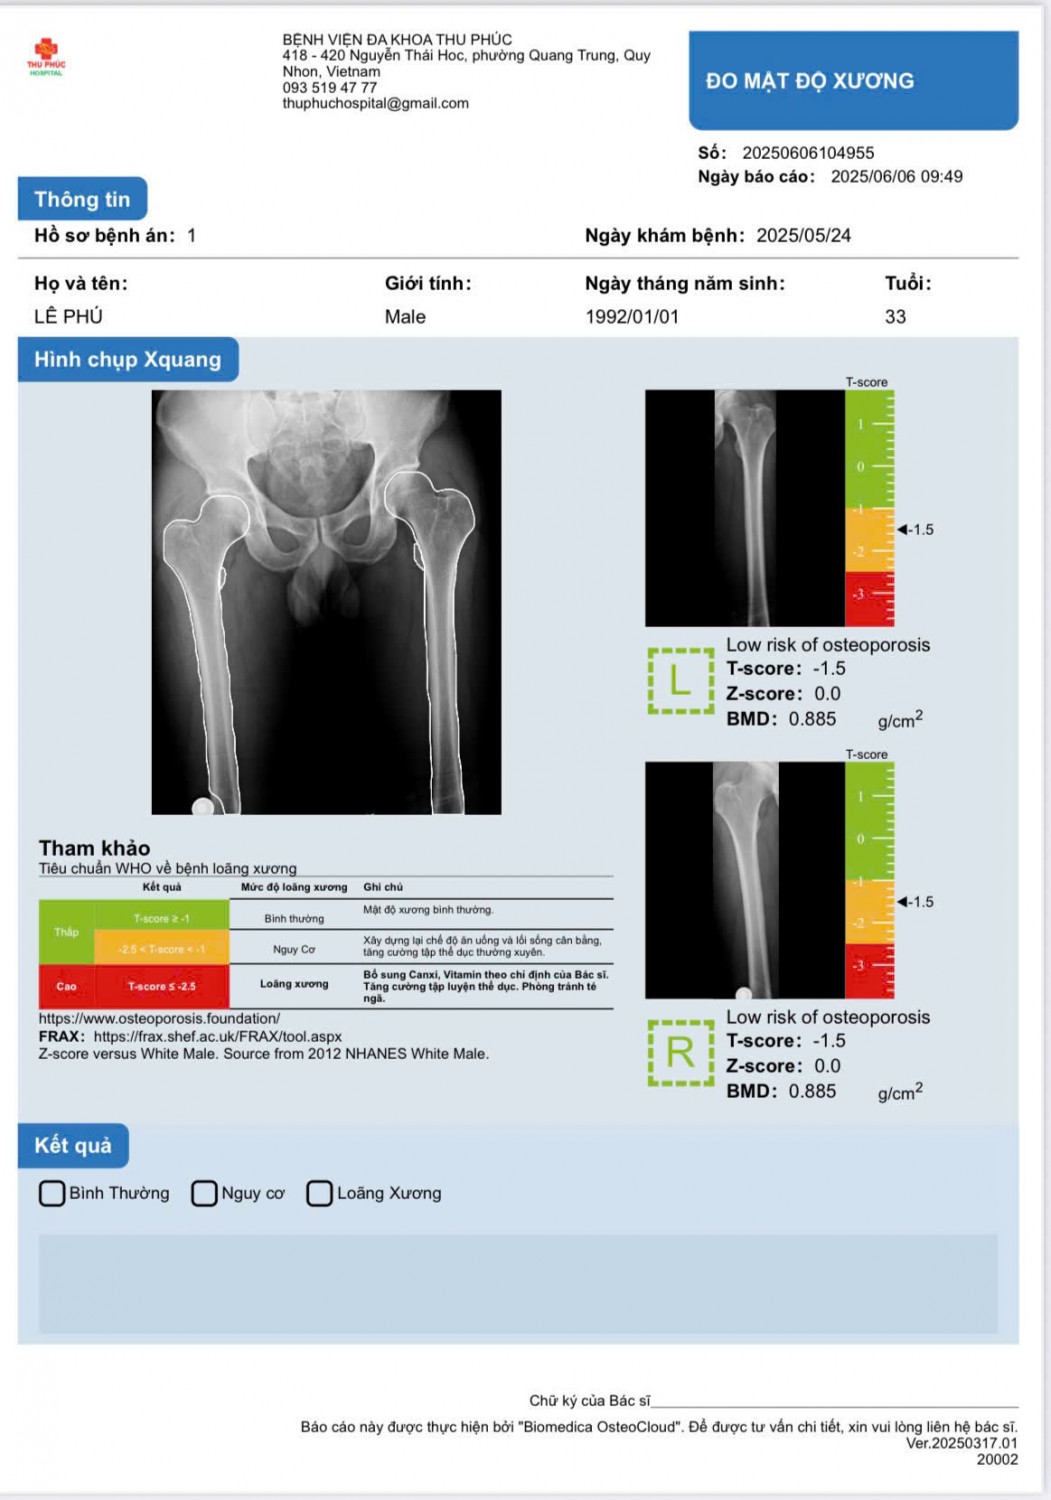

- Phát hiện sớm nguy cơ loãng xương: DEXA đo mật độ khoáng của xương, giúp bác sĩ đánh giá chính xác mức độ loãng xương và nguy cơ gãy xương trong tương lai.

- Độ chính xác cao: So với các phương pháp truyền thống, DEXA cho kết quả chính xác hơn, giúp bác sĩ đưa ra phác đồ điều trị phù hợp và hiệu quả.